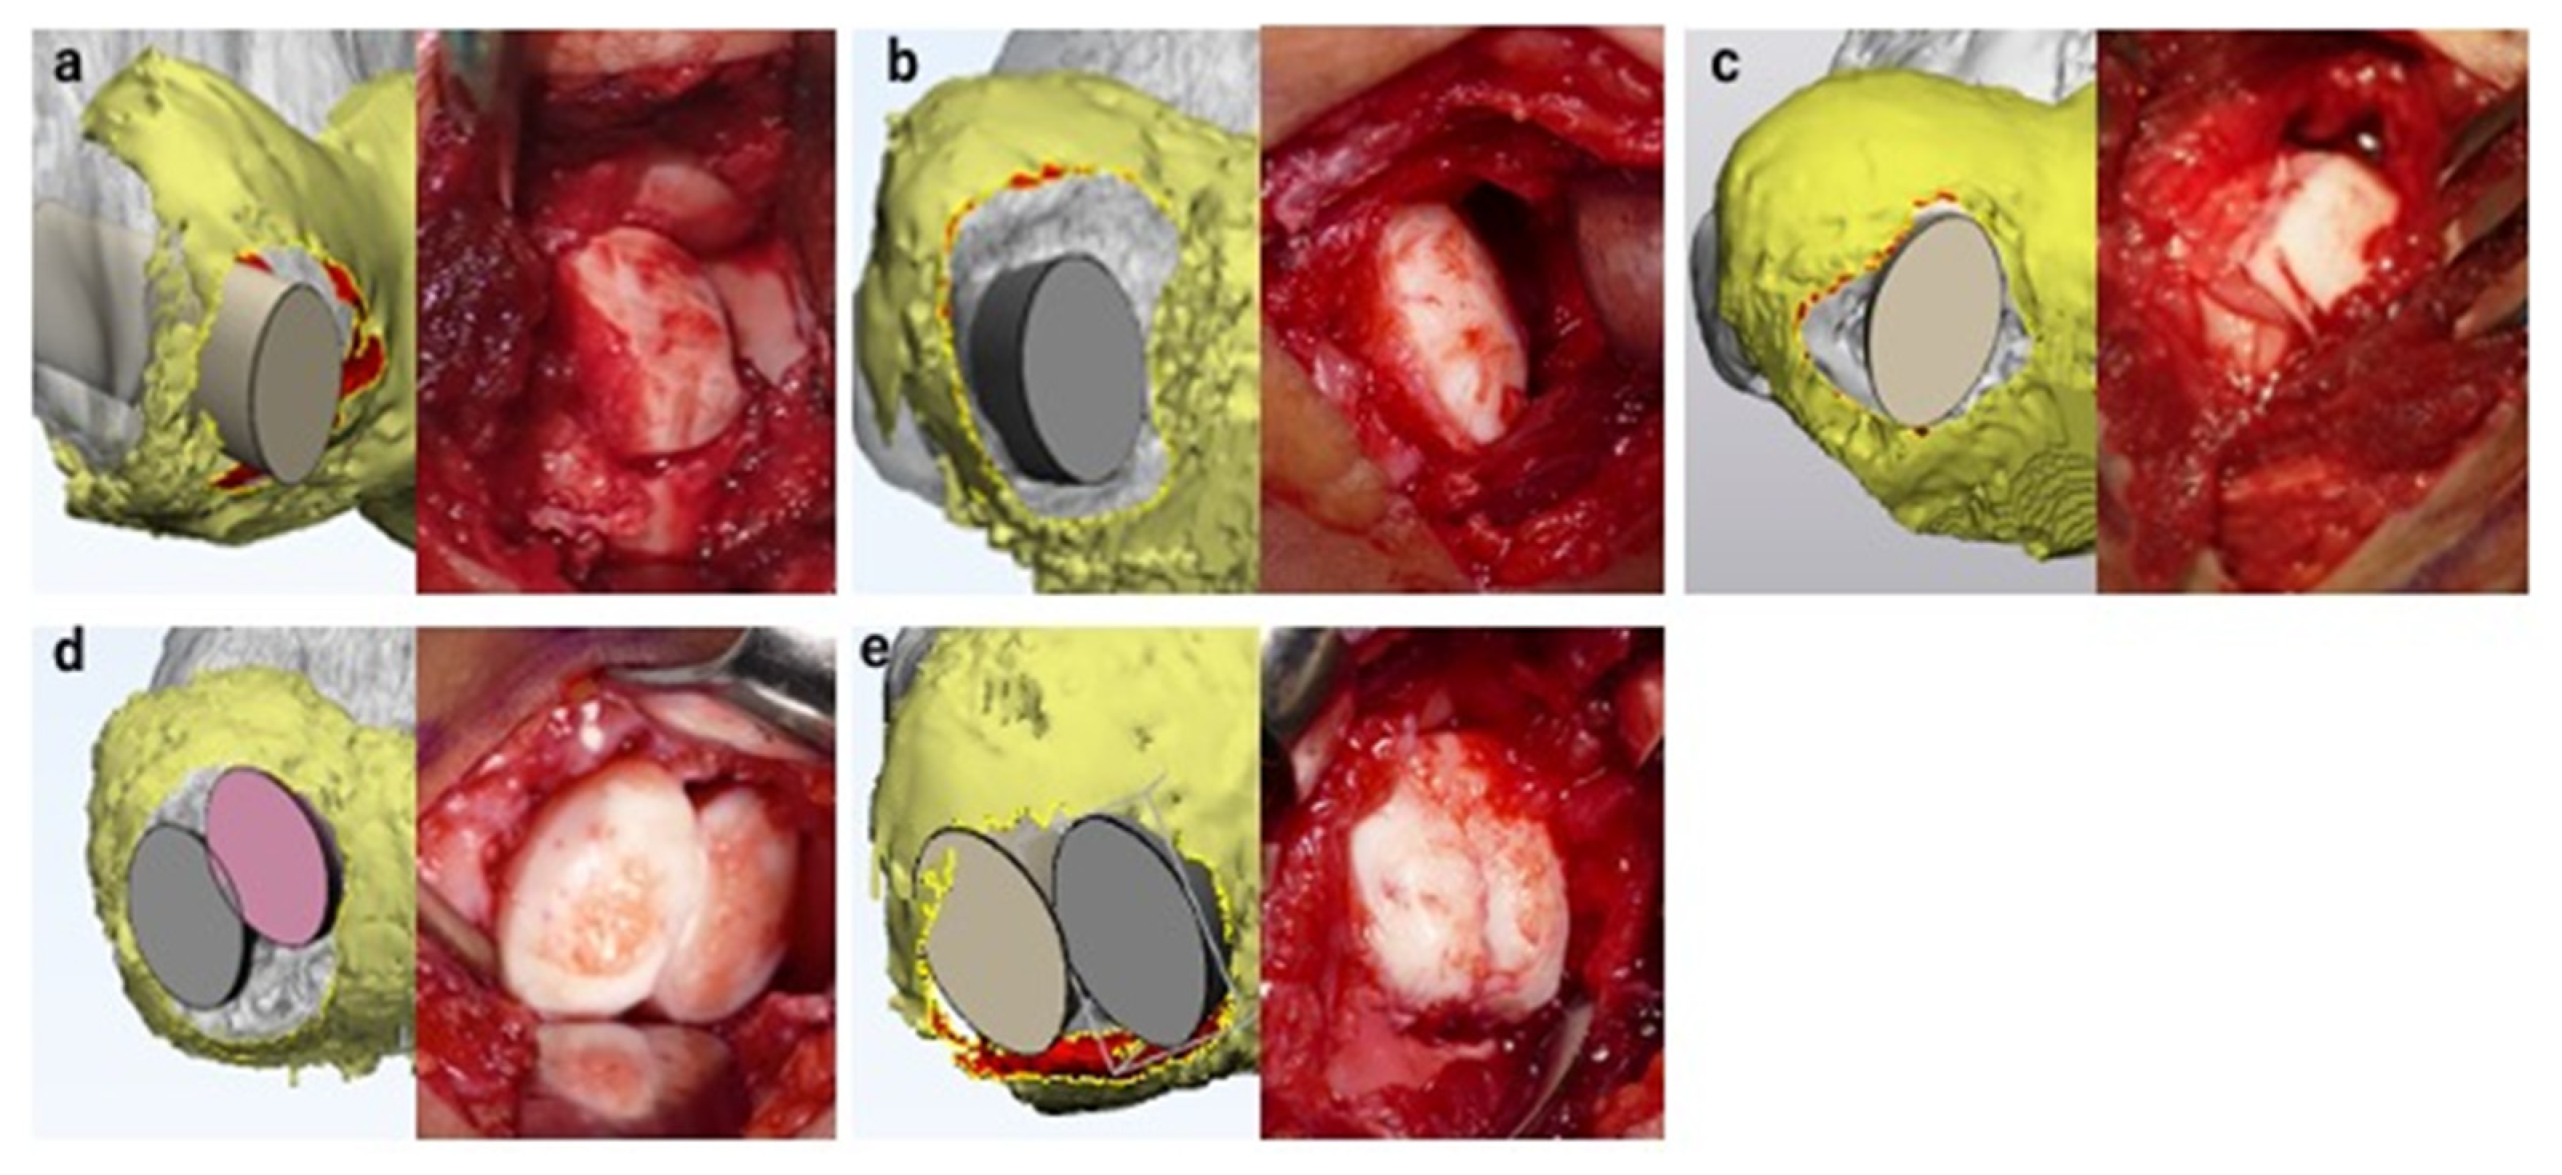

2.6. Surgical Simulation

3.3. Surgical Simulation

4. Discussion